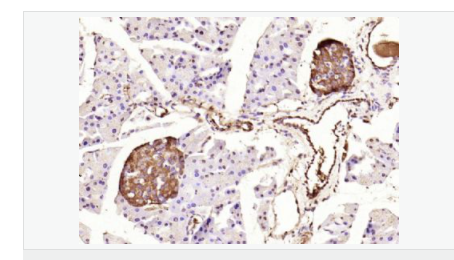

交叉反應(yīng):Human,Mouse,Rat(predicted:Dog,Pig,Cow,Rabbit,Sheep,GuineaPig) 推薦應(yīng)用:IHC-P,IHC-F,ICC,IF,Flow-Cyt,ELISA

| 產(chǎn)品應(yīng)用 | ELISA=1:5000-10000 IHC-P=1:100-500 IHC-F=1:100-500 Flow-Cyt=1ug/Test ICC=1:100-500 IF=1:100-500 (石蠟切片需做抗原修復(fù)) not yet tested in other applications. optimal dilutions/concentrations should be determined by the end user. |